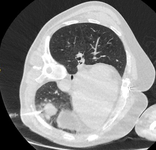

Cortes de tomografia computadorizada (TC) de dois casos com nódulos perifissurais benignos. Observe as margens lisas e a fissura adjacente normal e intacta

Do acervo de Dr. George Tsaknis, MD, PhD, FRCP (Londres), MRQA, MAcadMEd, PGCert; usado com permissão